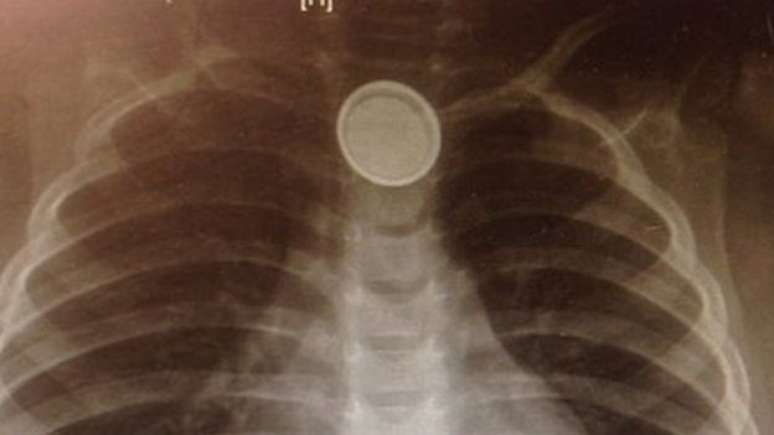

Valeria, de 3 anos, ficou doente de forma repentina em abril de 2015 - entre outras coisas, passou a recusar comida. Após cinco dias assim, ela foi submetida a um raio-x, que mostrou a causa do problema: uma bateria de relógio presa no esôfago.

Raio-x identificou bateria presa no esôfago de Catharina

Foto: BBC News Brasil